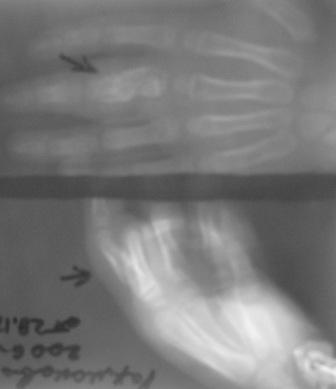

Уважаемые коллеги, на осмотре девочка 2006 г.рожд. Со слов матери 3мес. назад заметила припухлость основного фаланга 3-пальца, которая постепенно увеличилось до настоящего размера где-то в течении месяца, не болит, ребенка не беспокоит, признаки воспаления отсутствуют. Консультация онколога, биопсия - опухоль исключена (со слов матери), фтизиоортопед - тбс исключен. От основной фаланги 3 пальца к головке 4-пястной кости под кожей прощупывается хрящевидная ткань. Р-граммы от 10 декабря и 15 февраля, и фото прилагается. Что делать? Уважаемые коллеги, помогите! С уважением Абдурашид.

Добрый день, уважаемый Абдурашид. Судя по рентгенограмме, к сожалению не очень качественной, речь может идти о варианте дисхондроплазии, которую обозначают, как солитарную хондрому. Рентгенологически они проявляются в 3 вариантах-в виде интрамедуллярно и центрально расположенной энхондромы с вертеннобразным вздутием диафиза изнутри и истончением кортикальной пластинки, в виде опухоли, расположенной эксцентрично с заполнением части кортикального слоя и характерным костным козырьком, в виде экхондром, выступающих за пределы кости

Уважаемый Игорь Владимирович! Я очень рад Вас услышать! И в самом деле это один из вариантов дисхондроплазии ( т.н. болезнь Оллье), так как принесли результат биопсии: -"эмбриональный хрящевой ткань, симулирующий хрящевую опухоль"